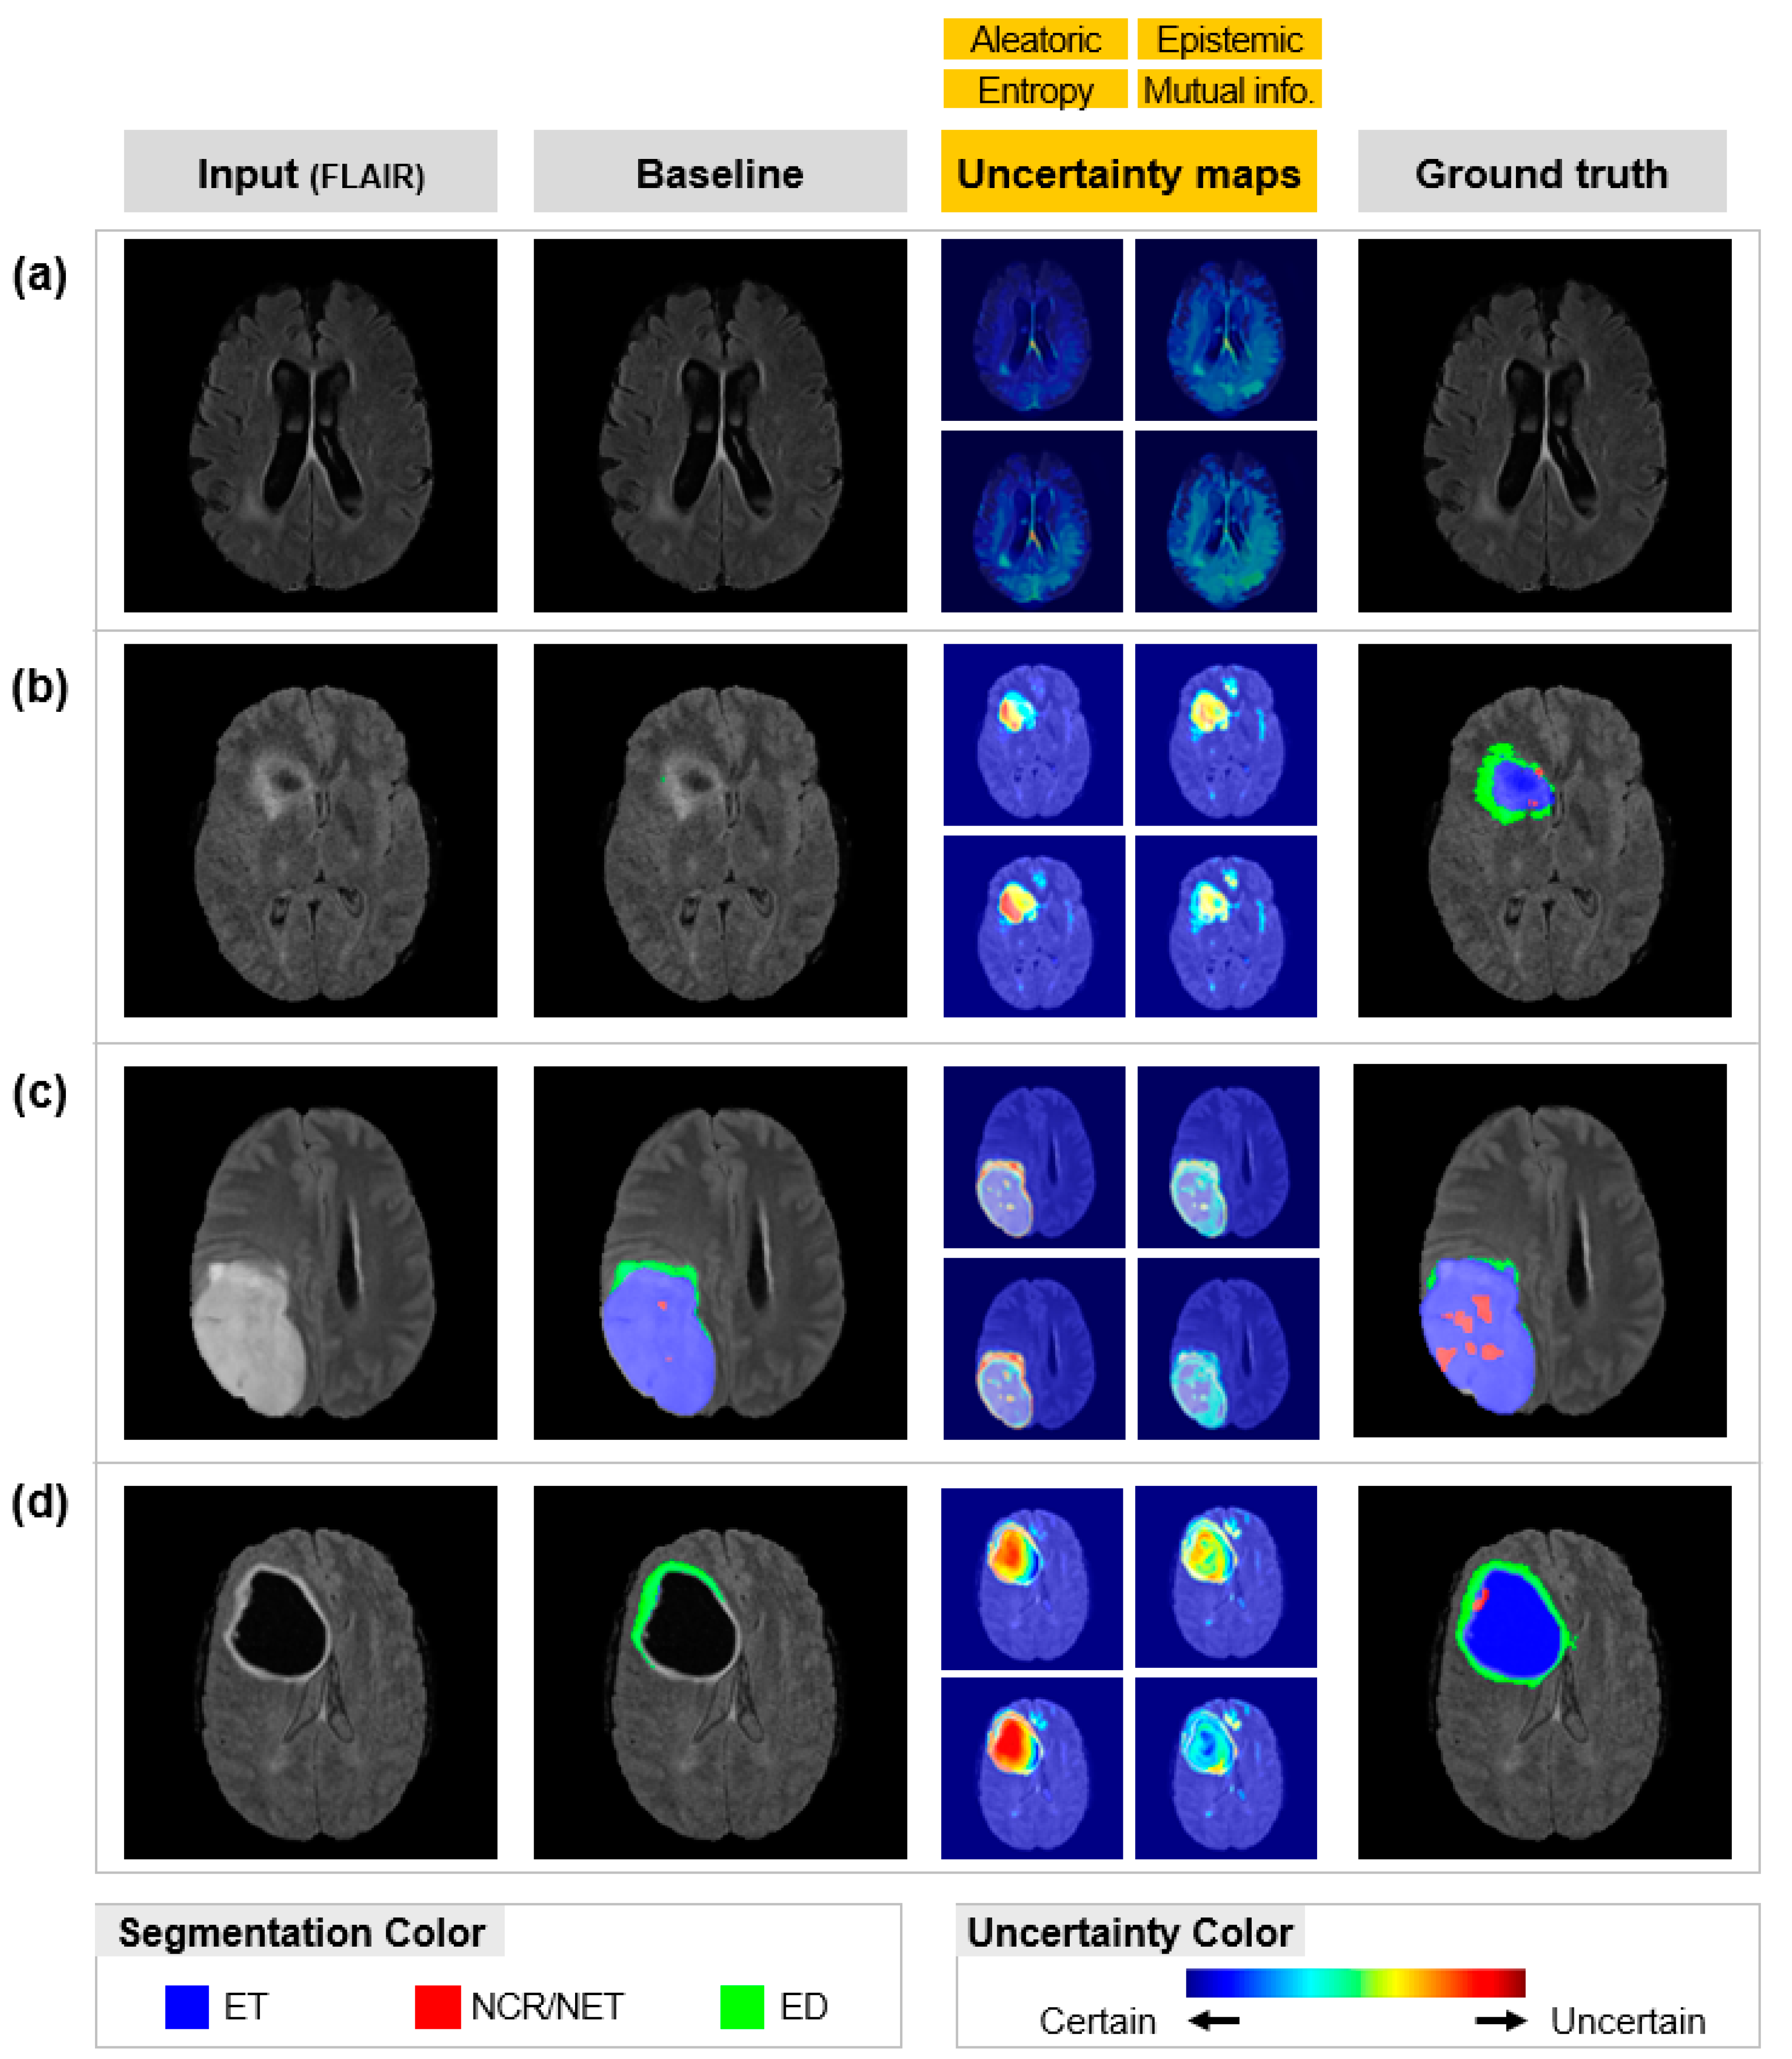

To find out the errors of the baseline model, we applied four different uncertainty measures, and the results are shown in Figure 4. It shows brain tumor segmentation and Uncertainty Maps (UMs), which show how uncertain the segmentations are. For example, red in the UMs denotes that those areas in the segmentation map are highly uncertain, and blue denotes that those areas are highly certain. These uncertainty measures, originated in statistics, were measured from data noise (Aleatoric and Entropy) and model imperfection (Epistemic and Mutual Information). These measures are widely utilized in various fields such as medical imaging to identify an algorithm’s reliability and to minimize its errors [14,20].

Figure 4.

Uncertainty quantification results: Automated segmentation results by baseline model, corresponding uncertainty maps, image, and manual segmentation by experienced neurologists (ground truth). Each scan is from a different patient. The color code of the segmentation map and uncertainty map is described below. Red in the uncertainty map means an uncertain predictive area, and blue means a certain predictive area. ET = enhancing tumor; NCR/NET = necrotic and non-enhancing tumor; ED = peritumoral edema. (a) Totally correct prediction and UMs. (b) Totally incorrect prediction and UMs. (c) Slightly incorrect prediction and UMs. (d) Moderately incorrect prediction and UMs.

As a result, baseline segmentation maps, corresponding UMs, ground truth, and MRI images (FLAIR) are illustrated in Figure 4. Our UMs were corresponding maps that indicate the uncertainty of baseline segmentation results. The ground truth images are the manual segmentations performed by experienced neurologists. The color bar in Figure 4 represents the level of uncertainty. Red means that the baseline prediction is uncertain and blue means that the baseline prediction is certain. The UMs of Figure 4a have a blue color, indicating that baseline prediction was certain. On the contrary, the UMs of Figure 4b–d have various colors, including blue to red, indicating that some part of the baseline prediction was uncertain. Uncertain areas (Figure 5b) are more likely to be incorrect predictions than certain areas (Figure 5a). False negatives also tend to have highly uncertainty values (Figure 5d). Therefore, the UMs are significant indicators in showing the reliability of the prediction model. Moreover, tiny and confusable lesions, such as necrotic and non-enhancing tumors, show high uncertainty values (Figure 5c). Because Epistemic and Mutual Information measures model weakness, these maps can suggest what we can learn from the model.